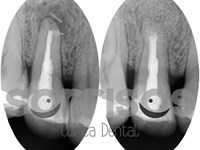

Para que este cambio sea posible, es necesaria una buena planificación, pero siempre precedida de un diagnóstico meticuloso, en el que se combinan fotografías, radiografías y estudio con escaneado tridimensional. Por eso, en nuestra clínica dental Sorrisos, en Pontevedra, analizamos con detenimiento cada caso particular, para poder llevar a cabo el tratamiento más adaptado a las necesidades de nuestros pacientes.